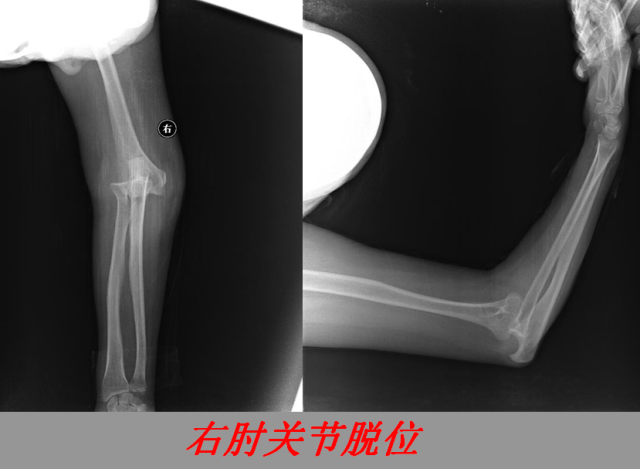

关节脱位篇

02

定义:关节脱位是暴力、关节感染、附近软组织挛缩或先天骨发育障碍造成的关节对位关系部分或完全脱离,即为半脱位或脱位。临床上以创伤性脱位*常见。